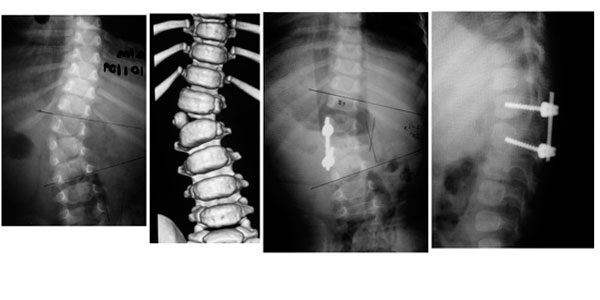

Paciente de 1 año y 8 meses con escoliosis congénita progresiva, se realizó resección de hemivertebra con colocación de tornillos transpediculares